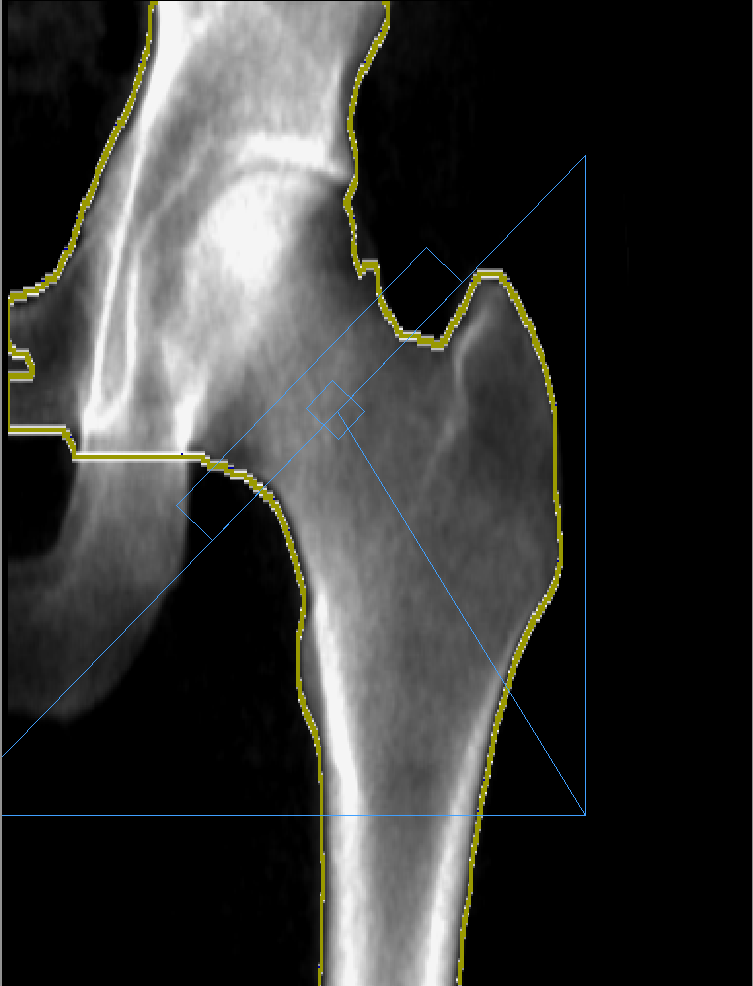

- Ортопедия. InAlyzer-AIR позволяет спланировать тактику лечения при эндопротезировании суставов.

- Хирургия. С помощью рентгеновского денситометра возможно получить трехмерное изображение костей и суставов для планирования хирургических вмешательств.